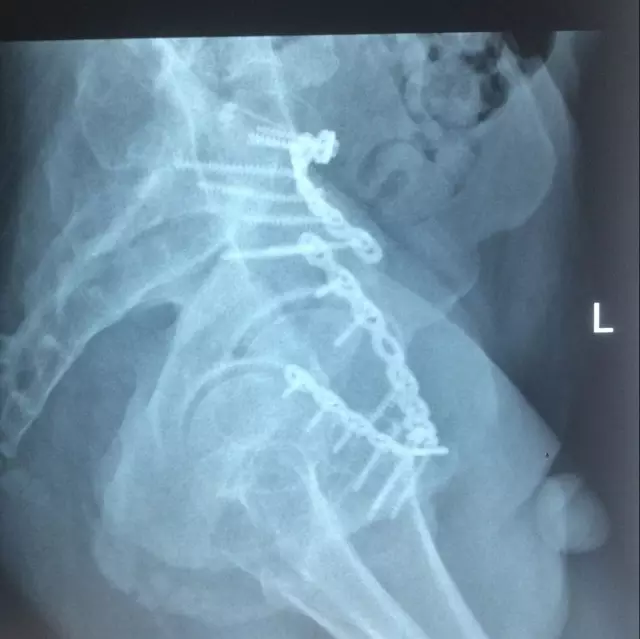

为此,科室在黄东永科主任为首的专科团队带领下,经过周密计划、分析讨论、总结过往的经验,制订了严密的手术方案,并得到了南方医科大学附属第三医院曾参军教授的指导,于8月20日在插管全麻下顺利为该患者施行了骨盆多发骨折的手术,术后效果较好,患者自觉满意。

患者术后复查X片情况

术后X片